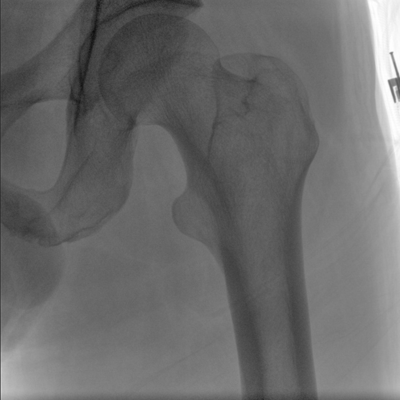

臨床適用科室:骨科、普通外科、矯形外科、創(chuàng)傷外科、泌尿外科、脊柱外科、疼痛外科、消化科、婦科等科室。

大尺寸動(dòng)態(tài)平板探測(cè)器,高DQE、低噪聲、圖像清晰。采用多分辨率圖像增強(qiáng)處理技術(shù),不同部位不同圖像處理算法,滿足客戶多樣化的需求。

采用智能變頻脈沖透視技術(shù),優(yōu)化圖像質(zhì)量的同時(shí)降低輻射劑量,呵護(hù)醫(yī)患健康